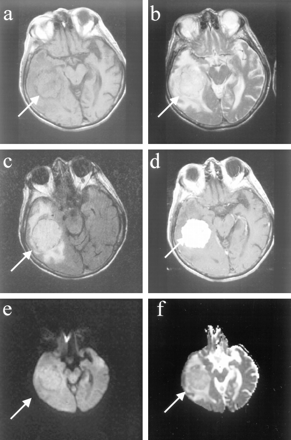

Five of these benign meningiomas had distinct histopathologic features. All of these meningiomas had the highest elevations in the diffusion constant (average 1.29 ± 0.22 × 10−5cm2/s), ranging in values from 1.07 to 1.8 × 10−5cm2/s (Fig 3, patient 14). These meningiomas tend to be hypointense on diffusion-weighted images and hyperintense on ADC maps. Histopathologic analysis revealed that three of these meningiomas represented a benign subtype of meningioma with unique features. One of these meningiomas had undergone microcystic change, a feature of the histologic subtype called the microcystic meningioma. Another meningioma was classified as a secretory meningioma, which is another distinct subtype characterized by marked edema in the surrounding brain parenchyma. The third subtype was an angiomatous meningioma.

Images of a patient (patient 14 in the Table) with a benign meningioma, distinct histopathologic subtype.

A, Axial T1-weighted image shows left frontal extraaxial mass with smooth margins and pseudocapsule sign.

B, Fast spin-echo T2-weighted image of the mass is isointense to cortex, with areas of hypointensity.

C, Fast fluid-attenuated inversion recovery image shows that the mass is isointense to cortex.

D, Homogeneous enhancement and “dural tail” are seen on the contrast-enhanced axial T1-weighted image.

E, Diffusion-weighted image shows that the meningioma is hypointense.

F, On the ADC map, the lesion is predominantly hyperintense, with areas of isointensity. The diffusion constant of this meningioma was elevated (1.07 × 10−5 cm2/s). This is greater than a 25% elevation compared with normal brain parenchyma. Histopathologic analysis revealed that this represented a secretory meningioma, which produces brain parenchymal edema (seen best by the fast fluid-attenuated inversion recovery) and which has prominent pericytic proliferations.